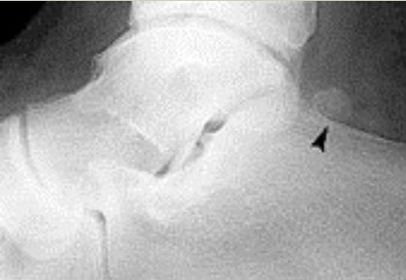

What disease is this? What does the arrow indicate? | Rheumatoid arthritis. Arrow = Bone erosion secondary to inflammation of retrocalcaneal bursa. |